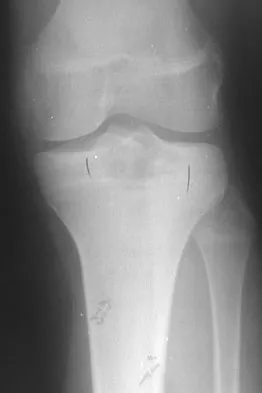

Question 61

A 16-year-old football player sustains a direct blow to the anterior aspect of his flexed right knee. Examination reveals a contusion over the anterior tibial tubercle and a small effusion. MRI scans are shown in Figures 33a through 33c. What is the most likely diagnosis?

Explanation

The MRI scans show disruption of the fibers of the PCL. Patients sustaining an isolated acute PCL injury can present with only minimal discomfort and have full range of motion. When examination reveals a contusion over the tibial tubercle and discomfort with the posterior drawer examination, with or without instability, a possible injury to the PCL should be considered. In acute injuries, the reported accuracy of MRI imaging for diagnosing PCL tears ranges from 96% to 100%. Resnick D, Kang HS: Internal Derangement of Joints: Emphasis on MRI Imaging. Philadelphia, PA, WB Saunders, 1997, pp 699-700. Harner CD, Hoher J: Evaluation and treatment of posterior cruciate ligament injuries. Am J Sports Med 1998;26:471-482.